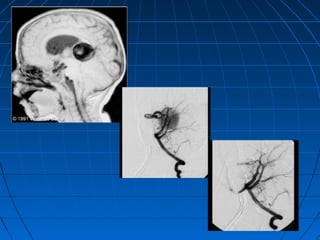

 42 yaşında erkek hasta42 yaşında erkek hasta

 BaşağrısıBaşağrısı (kronik)(kronik)

 Nörolojik olarak intaktNörolojik olarak intakt

CERRAHİCERRAHİ

 Sağ pterional trans-sylvianSağ pterional trans-sylvian

transtentorial pre- and para-transtentorial pre- and para-

pedünküler yaklaşımpedünküler yaklaşım

 PCA Anevrizması kliplendiPCA Anevrizması kliplendi